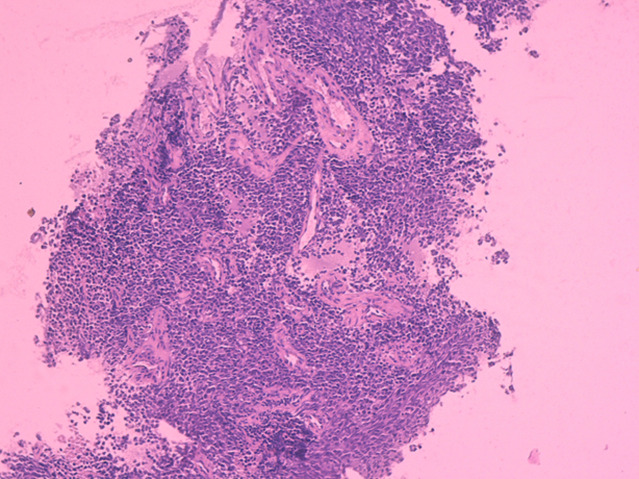

Ewing家族软组织肿瘤(EFT)代表了一种不确定组织发生的肿瘤谱,发生在没有骨累及的软组织中。它们包括骨骼外尤文氏肉瘤和原始神经外胚层肿瘤。这些肿瘤在形态上与骨骼系统的尤文氏肉瘤难以区分。已知易位相关肿瘤,它们具有共同的非随机易位,导致EWSR1基因在22q12区域与ETS家族转录因子中的一个成员融合。EFT主要发生在青少年和30岁以下的年轻男性中,几乎可以出现在任何地方,但最常见于四肢的深层软组织。本研究报告一例罕见的发生在14岁男孩上臂的EFT病例,他表现为右臂肿块疼痛发展了6个月,同时强调了这种罕见疾病的主要组织学,免疫组织化学和分子特征,以及相关诊断方法的原始流程图,用于鉴别诊断。

The Ewing family tumors (EFT) of soft tissue represent a spectrum of neoplasms of uncertain histogenesis, arising in soft tissue without bone involvement. They include Extraskeletal Ewing Sarcoma and Primitive Neuroectodermal Tumor. These tumors are morphologically indistinguishable from Ewing sarcoma of the skeletal system. Known to be translocation-associated neoplasms, they share a common non-random translocation leading to the fusion of the EWSR1 gene on the 22q12 region, with one of the many members of the ETS family of transcription factors. Occurring mainly in adolescents and young men under the age of 30, EFT´s may arise virtually anywhere, but are most common in deep soft tissues of the extremities. The purpose of this work is to report a rare case of an EFT arising in the upper arm of a 14-year-old boy, who presented with a painful right arm mass evolving for 6 months, while highlighting the main histological, immunohistochemical and molecular features of this rare condition, along with an original flow chart of a relevant diagnostic approach for differential diagnosis.